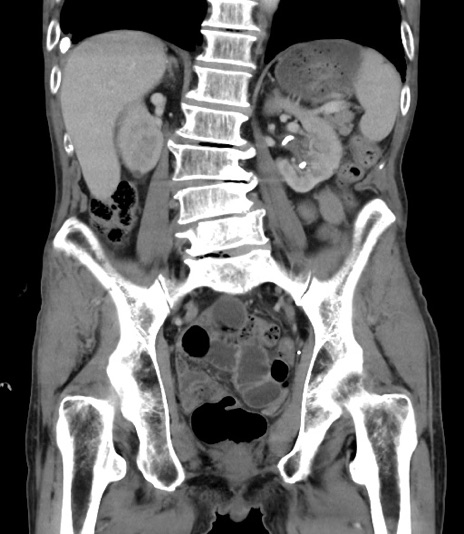

症例3(冠状断像)

【症例】 70歳代男性

【主訴】右鼠径部腫瘤、疼痛

【現病歴】本日朝より上記主訴あり、受診。

【既往歴】膀胱癌にて膀胱全摘、両側尿管皮膚瘻

【データ】WBC 5600、CRP 0.56